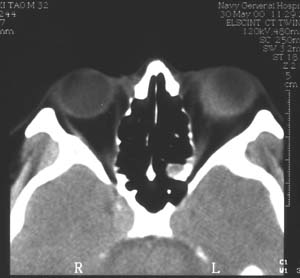

1 患者男性,32岁。998月发现左眼球突出,当时按眶内炎症治疗无效9912月左眼开始充血,反复发作(后来仅间隔1-2天),头痛。曾按“结膜炎、眼眶炎症”等治疗无效。20004月经CT检查发现左眼球外侧肿物,诊断:眼内肿物、眶内炎性假瘤?随来我院。入院检查:视力(戴镜)右眼1.0,左眼0.3,不能矫正。左眼睑肿胀,结膜混合充血,结膜下血管怒张(图1)。角膜正常,屈光间质清楚。眼底为高度近视眼底表现(-10D),眼球壁内下方600-900自视盘下方开始隆起(约+6D)。眼球突出4mmB超及标准化A超显示左眼球内下方及下方巩膜肥厚,最厚处达7mm,可见明显筋膜囊水肿(图2)。CT显示左眼球内下方巩膜增厚,并向眼内隆起,筋膜囊水肿(图3)。

图3 CT显示左眼球内下巩膜增厚并向眼内隆起,合并筋膜囊水肿边界欠清楚